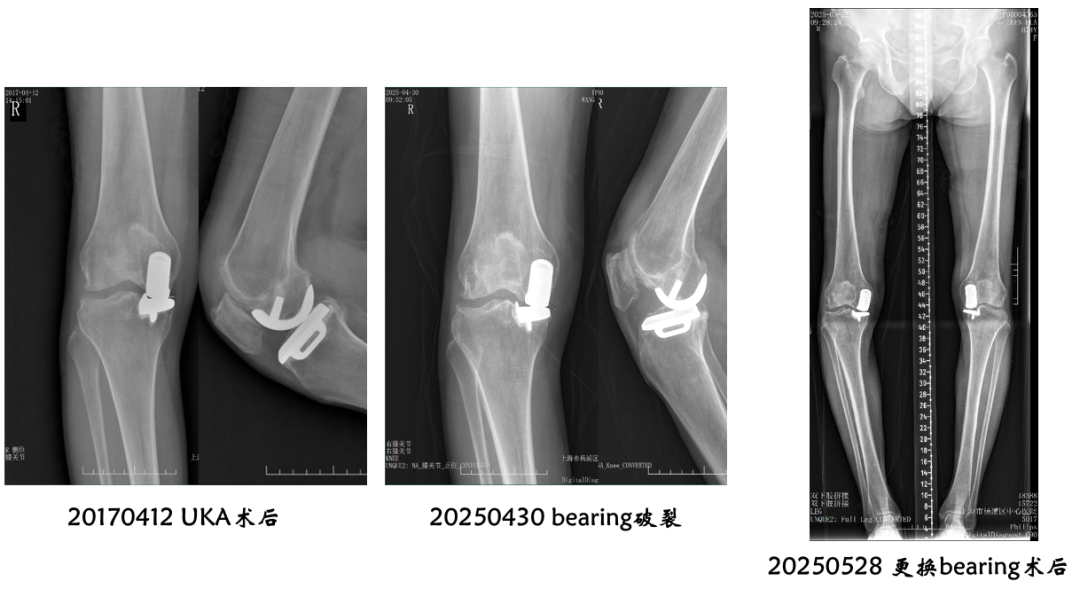

病例2:Bearing 破裂( X-ray正位)

解读:两个点都在内侧

病例2:Bearing 破裂( X-ray侧位)

解读:股骨假体与胫骨假体间隙还存在,在图像放大4倍情况下,才依稀看到模糊的点.

病例2:Bearing 破裂

病例2:Bearing 破裂的处理